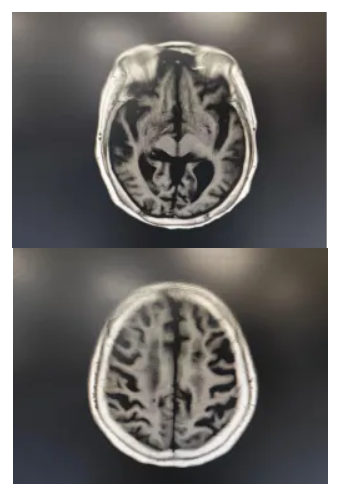

“第3天,他能睁眼了!第4天,能简单遵嘱握手!”张先生的妻子激动地说。经过近10天的治疗,患者意识完全清醒,语言功能和肢体活动逐步恢复,复查头颅MRI未见明显脑损伤,顺利转出ICU。

MRI部分成像